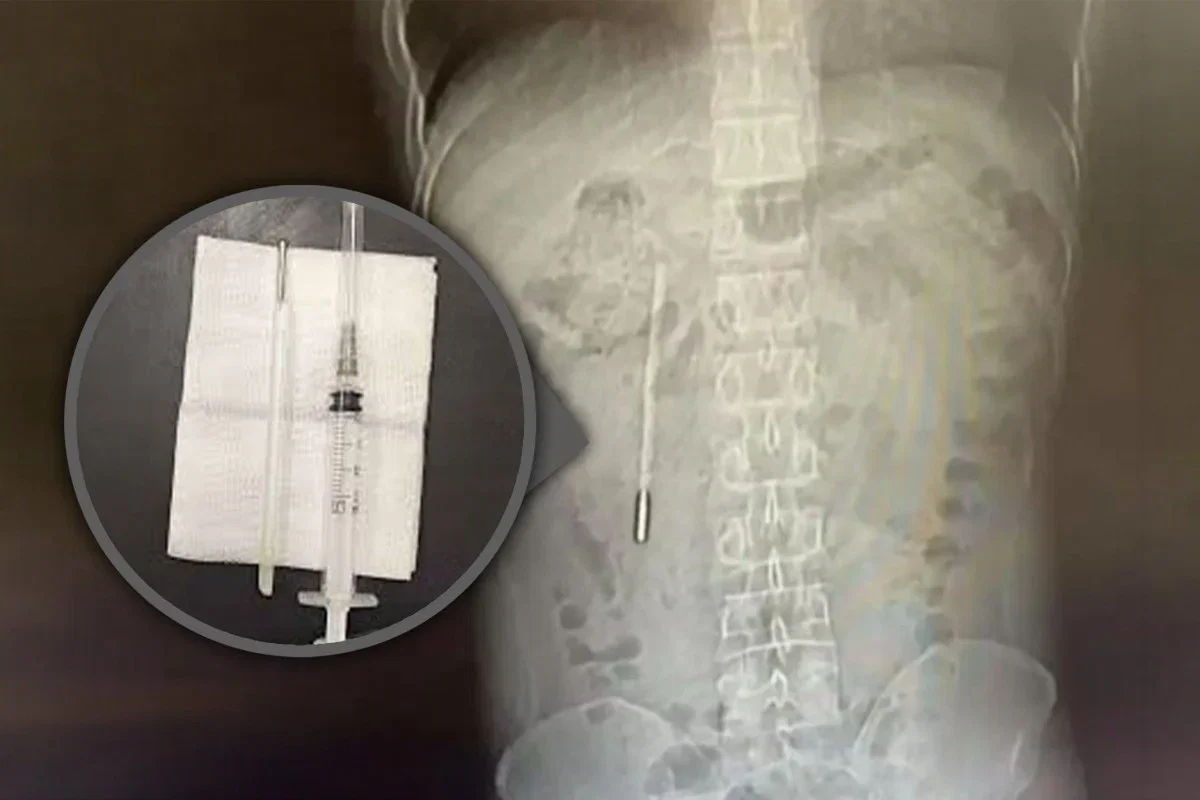

במהלך השובע האחרון וואנג פנה לבית החולים המסונף לאוניברסיטה הרפואית בוונג'ואו לאחר שסבל מכאבי בטן עזים. במהלך הבדיקות, הרופאים נדהמו לגלות בצילום חפץ זר במעי התריסריון שלו, שנחשד מיידית כמדחום כספית. המצב היה רגיש ומסוכן, שכן קצה המדחום לחץ ישירות על דופן המעי, מה שיצר סיכון גבוה לנקב ולדימום פנימי חמור.

למרות המורכבות הרפואית והמיקום הרגיש ליד דרכי המרה, הצליחו המנתחים לבצע הליך מדויק ולהוציא את המדחום בתוך 20 דקות בלבד. לאחר השליפה, התברר כי המדחום נותר שלם לחלוטין בתוך גופו של וואנג במשך כל השנים, אם כי סימני המדידה עליו דהו עם הזמן.